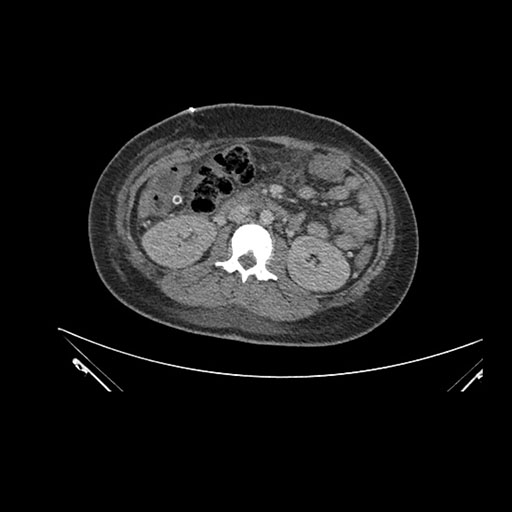

Imaging Analysis

Look through the patient's CT scan to identify any areas of concern for the necessary procedure.

Axial Arterial

Based on initial findings, which issue(s) would you be most concerned about?